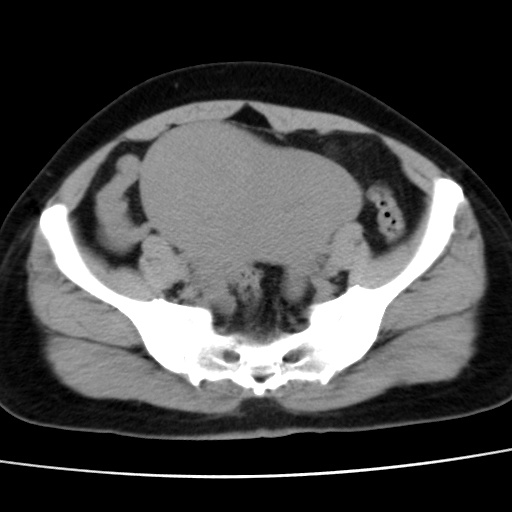

子宫多发肌瘤吗

多发性子宫肌瘤.

考虑多发子宫肌瘤,子宫直肠窝双囊性占位,另直肠周围脂肪密度增高,不知有何病史

支持考虑多发子宫肌瘤~!子宫直肠陷凹积液?

支持考虑多发子宫肌瘤~!子宫直肠陷凹积液!

子宫肌瘤,宫体部后方见液性密度影,是肠道还是子宫与直肠陷窝积液不好说,我觉得它的位置有点高

支持考虑多发子宫肌瘤!子宫直肠陷凹积液!

患者发热,而子宫直肠窝液性灶有明显边缘且局限且囊性,不除外为包裹性积液或脓肿

支持考虑多发子宫肌瘤,子宫直肠陷凹积液可能。

1)考虑子宫肌瘤可能性大。2)子宫后方囊性占位性病变,不排除卵巢囊肿可能。

考虑多发子宫肌瘤。子宫后方囊性占位性病变,不排除卵巢囊肿可能。